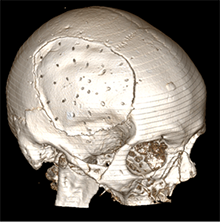

6 pav. Perforacijos KPL

Po pusės metų vyras konsultuotas ambulatoriškai planine tvarka. Atlikus GKT, nustatyta nedidelė lėtinė SDH dešinėje pusėje parietaliai. Po mėnesio suplanuota atlikti KP. Operacijos metu suformuotas kranioplastikos lopas (KPL) iš kraniocemento. Atlikta daugybinių KPL perforacijų (6 pav.), KPL fiksuotas prie kaukolės 10 siūlių. Kitą dieną po operacijos atlikta kontrolinė GKT (7 pav.): po KPL nustatyta hemostatinė medžiaga ir ~20 mm storio ūminė epidurinė hematoma. Vidurio struktūrų dislokacija į kairę – iki 3 mm. Dešinėje pusėje, poodyje – pooperacinė sankaupa su pakraujavimu. Tą pačią dieną atlikta skubi operacija epidurinei ir periostinei hematomoms pašalinti. Aktyvaus kraujavimo operacijos metu nenustatyta. KPL grąžintas, minkštieji audiniai susiūti (8 pav.). Po operacijos paciento būklė buvo stabili, patologinių neurologinių simptomų nenustatyta. Praėjus 2 savaitėms, esant sklandžiai pooperacinei eigai, vyras perkeltas į slaugos ligoninę.

Fenestracijų reikšmė

Dėl anksčiau gydytų EDS, susidariusių atlikus KP, klinikinėje praktikoje KPL buvo atlikta daugybinių perforacijų. Mokslinės literatūros duomenimis, KPL, turinčio fenestracijų, daug geresnės išeitys negu KPL, neturinčio fenestracijų [11], nes EPS susisiekia su subgaliniu tarpu ir dėl slėgių gradiento rezorbuojasi į minkštuosius audinius. Per padarytas skylutes EDS susisiekia su subgaliniu tarpu, seroma labiau kaupiasi po minkštaisiais audiniais negu epiduraliai. Nustatyta, kad aponeurozei būdinga gera rezorbcija, todėl EDS linkusios regresuoti [12].

Straipsnyje aptariamu atveju paciento KPL skirtinas mažiausiai (75 cm2) grupei, kuriai būdinga minimali infekcijos atsiradimo rizika (13 pav.), tačiau operacijos metu vis tiek buvo paimtas mikrobiologinis pasėlis infekcijai ekskliuduoti. Mokslinėje literatūroje taip pat pristatomas siekis tirti skirtingų pirminių galvos smegenų hematomų, po kurių reikėjo atlikti kraniektomiją, koreliaciją su EDS, tačiau reikšmingų rezultatų negauta [8].